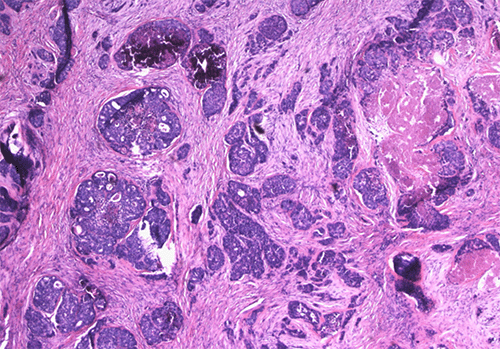

Final pathology revealed a 3.5 cm mixed neuroendocrine-non-neuroendocrine neoplasm (MiNEN) with perineural invasion (Figures 2A and 2B); resection margins were negative for malignancy. Ten lymph nodes were resected, and all were negative for malignancy.

Figure 2. Histopathologic Features of of MiNEN Tumor with Distinct Morphology. Published with Permission

(A) H&E stain (40x magnification) demonstrating the infiltrating tumor cells with a nested and cribriform architecture, patchy tumor necrosis, and calcifications

(C) Mucicarmine stain (200x magnification) highlighting mucin production by the tumor, confirming the presence of an adenocarcinoma component

The tumor consisted of 35% WHO grade 3, well-differentiated neuroendocrine tumor with a 30% proliferation index, and 65% poorly differentiated adenocarcinoma with an 80% proliferation index. The tumor was staged as pT3N0. Immunohistochemical staining showed the tumor to be positive for AE1/AE3 and variably immunoreactive for synaptophysin, chromogranin, and INSM1. Scattered tumor cells were positive for CK20, and the tumor was negative for CK7. Following discussion at the multidisciplinary tumor board, adjuvant FOLFOX chemotherapy was recommended. To date, surveillance imaging has shown no evidence of recurrence or metastatic disease within the abdomen.